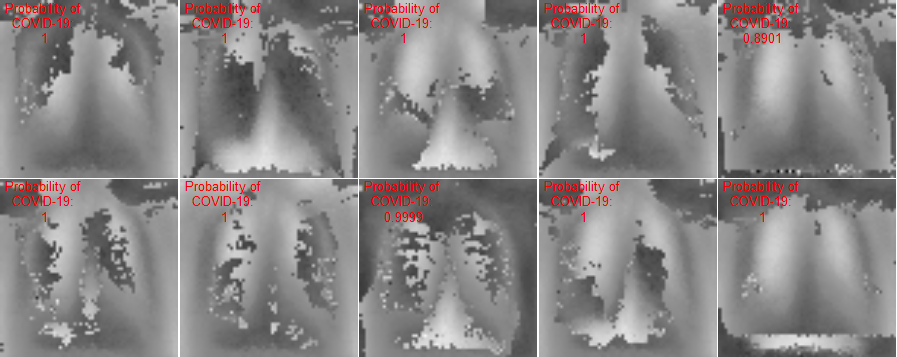

This section presents visualization of the proposed architecture. These visualizations are presented in Figure 5. Unlike Figure 2 that is an executive summary with each position representing many samples, these visualizations in Figure 5 are sample-wise plots. In other words, the 10 original images that are sized 128 by 128 in Panel A and Panel B are the same samples in the second row, 1st Conv. Layer, and the third row, 2nd Conv. Layer.

Visualization Interpretation The plot in Figure 5 of the original images for COVID-19 patients has grey and cloudy textures in chest area. Because an X-ray picture is at its brightest when most of the light beams emitted are bounced back from the object, we can observe bones to be the color “white” while the margin to be completely “black”. For muscle and organs inside human body, X-ray beams that are emitted can only partially be collected and this causes the greyscale on the X-ray images in chest area. For COVID-19 patients, there are grey and shaded area in the chest X-ray pictures. This is due to the inflammatory fluid when patients exhibit pneumonia-like symptoms. The fluid inside chest area is a consequence of human immune system fighting against outside diseases. This shaded (as seen in Panel A of Figure 5) prevents us from observing the clear location of lungs. This is different in Panel B where the lung areas are dark and almost black, because a healthy lung is filled with air (i.e. normal cases and X-ray image presents color black). The black and white contrast in the two panels is directly related to how much inflammatory fluid there is in human lungs. This contrast translates to greyscale on pictures and it is directly related with COVID cases and non-COVID cases (i.e. response variable ). The same contrast can be seen using the new variables (these are ’s based on equation 4) in the 1st Conv. Layer (sized 61 by 61). For COVID-19 patients, the lung area is cloudy and unclear while the healthy cases it is clearly visible. This is not a surprising coincidence because the proposed new variable modules, ’s, are engineered using equation 4 which relies on the response variable in training set. The images sized 61 by 61 from the proposed algorithm is a direct translation of not only the original pixels but also response variable. In other words, this visualization presents how I-score sees image data.

| Row (a) |  |

|

| 1st Conv. Layer: 61 by 61 | 1st Conv. Layer: 61 by 61 | |

| (Starting Point = 6, Window 2 by 2, Stride = 2) | (Starting Point = 6, Window 2 by 2, Stride = 2) | |

| Remark: variables | Remark: variables | |

| Same 10 images above with 3,721 variables | Same 10 images above with 3,721 variables | |

| Labels predicted using Model 1 | Labels predicted using Model 1 | |

| Row (b) |  |

|

Discussion for Figure 5.

This figure presents visualization summary for 10 randomly sampled images from COVID class and non-COVID class (each has 10). Panel A is for COVID patients and Panel B is non-COVID people. The first row plots the original images that are sized 128 by 128. The 1st Conv. Layer generates new variables. We plot the same 10 images from both classes using these 3,721 variables in the second row. We also print the predicted COVID probabilities on top left corner of each image. The 2nd Conv. Layer generate variables. We plot the same 10 image samples from both classes using these 900 variables in the third row. We also print the predicted COVID probabilities on top left corner of each image assuming using only these 900 variables as predictors. The plot of the original images for COVID-19 patients has grey and cloudy textures in chest area. This is due to inflammatory fluid when patients exhibit pneumonia-like symptoms. This shaded (as seen in Panel A) prevents us from observing the clear location of lungs. This is different in Panel B where the lung areas are dark and almost black which means the lung is filled with air (i.e. normal cases). The black white contrast in the two panels is directly related to how much inflammatory fluid there is in human lungs which translate to greyscale on pictures. The same contrast can be seen using the new variables (these are ’s based on equation 4) in the 1st Conv. Layer (sized 61 by 61). For COVID-19 patients, the lung area is cloudy and unclear while the healthy cases it is clearly visible.

|

Discussion for Figure 5.

Original Images to 1st Conv. Layer. The input images are sized 128 by 128. With the 1st Conv. Layer constructed, we have new variables. We trace back to the same samples as shown in the first row of Figure 5 and use these 3,721 variables only. When we plot these samples with these new variables, we resize them back in matrix form of 61 by 61. Panel A is for COVID class and Panel B is for non-COVID class. In addition, we use Model 1 in Table 4 to produce the texts that states predicted probability of COVID class. The red color implies ground truth to be COVID class (Panel A) and the green color implies ground truth to be non-COVID class (Panel B).